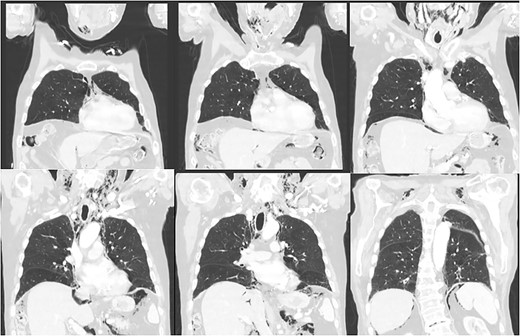

His vitals were stable on presentation. Physical exam was significant for weakness, tachypnea, and wheezing. He had no appreciable subcutaneous emphysema on clinical exam. Workup in the emergency department was remarkable for increased white blood cell count (17.0 K/uL). EKG showed no acute changes and cardiac enzymes were within normal limits. Computed tomography (CT) of the chest, abdomen, and pelvis with contrast was obtained, demonstrating acute sigmoid diverticulitis with extensive retroperitoneal air originating next to the sigmoid colon and multiple small collections of fluid. The pneumoretroperitoneum was continuous with pneumomediastinum and cervical emphysema (Figs 1 and 2). He was diagnosed with perforated diverticulitis and operative intervention was recommended.

CT scan of the abdomen and pelvis demonstrating perforation of the sigmoid colon and free gas in the retroperitoneum and mediastinum.